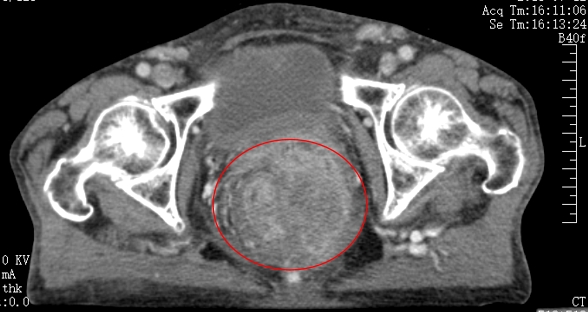

放疗前

放疗后